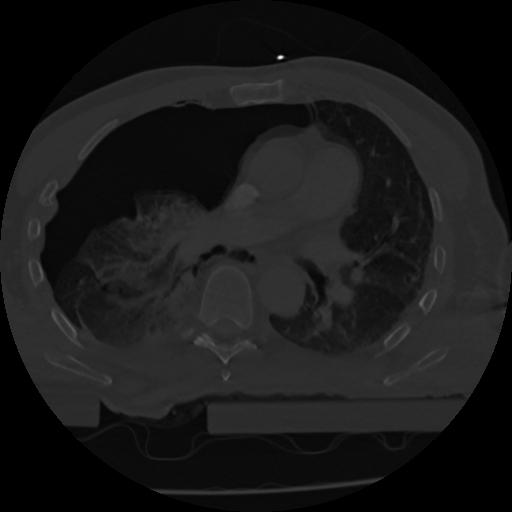

22 ANGIO,CE,Vol,0.5,ANGIO,,